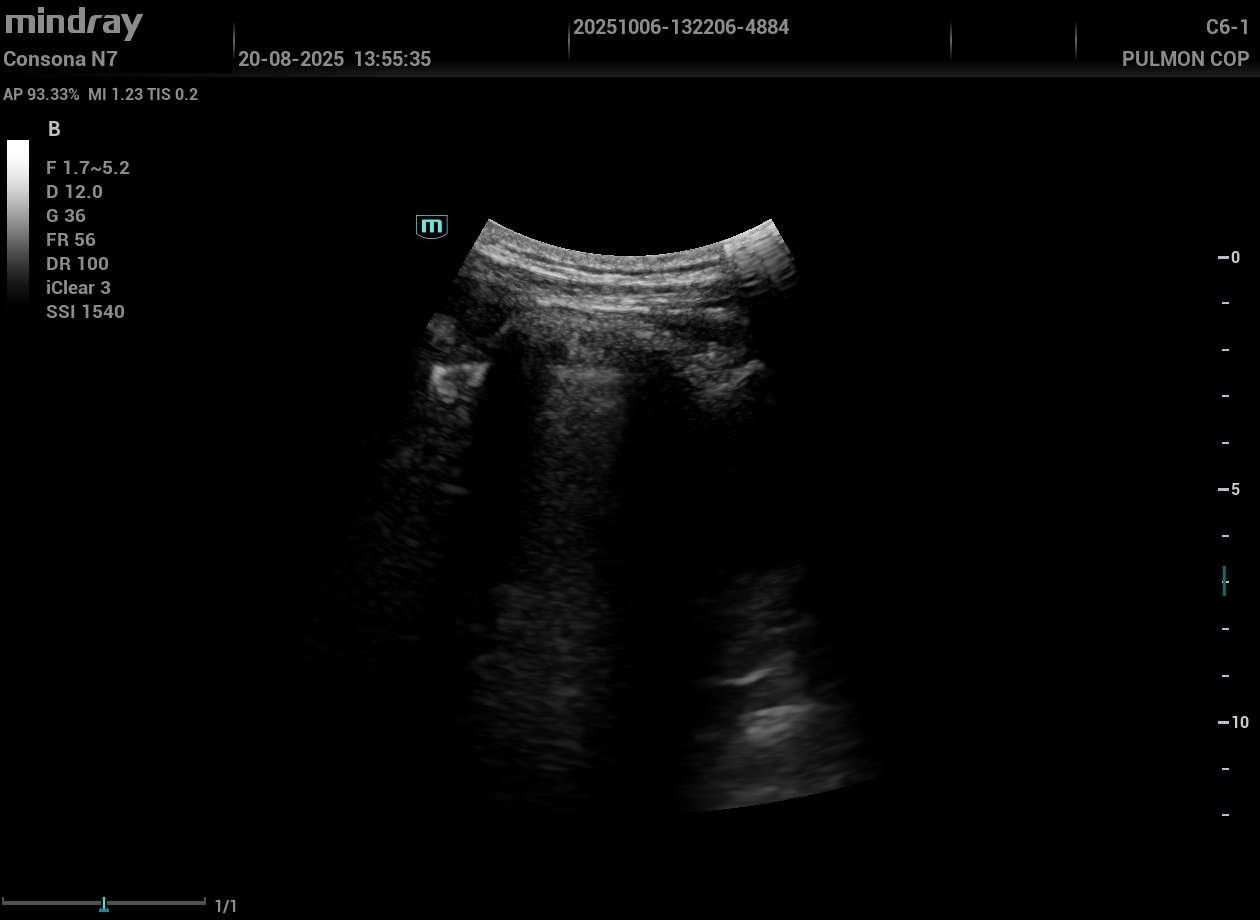

Hallazgos ecográficos

Eco pulmonar: colección anecoica con pérdida parcial del deslizamiento; compatible con derrame pleural de cuantía moderada.

Inicialmente, diagnóstico ecográfico de rotura fibrilar, manejo conservador. Posteriormente, ante dolor pleurítico y hallazgo ecográfico de derrame, primera derivación a Urgencias. Tras persistencia clínica, solicitud de Dímero D y segunda derivación como sospecha de TEP. Ingresa a cargo de Neumología iniciando anticoagulación con enoxaparina.